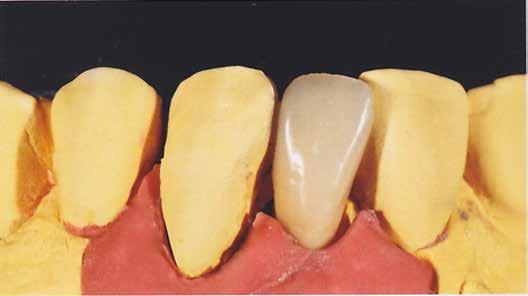

Massimiliano Trombin, dr. Roland Mantsch, Lorenzo Willsch (Németország) 1. a kép 1. kép 2. kép 3. kép

Az egyszárnyú ragasztott híd mellett döntöttünk (1. a kép)

Mivel a szemfogak általában nagyon közel vannak az antagonistához, kettes pótlására a szárnyat inkább a nagymetszőre szoktuk tervezni. Ehhez persze invazív preparációra van szükség – érintetlen fogak esetén ez lehetőleg kerülendő.

A bemutatott esetben azonban könnyen döntöttünk, mivel a szemfog disztális részén nagy tömés volt. A defektust bevontuk az eset megoldásába.